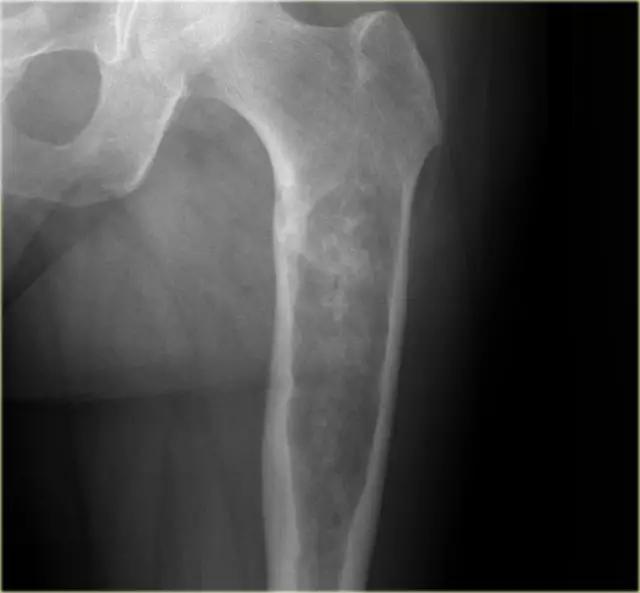

上图为部分边界欠清的溶骨性病变,伴有内皮层扇形(endosteal scalloping)。瘤体内存在软骨样基质的云状钙化。这些影像学表现与病灶大小有利于软骨肉瘤的诊断。

上面两个其他病变,确诊是软骨肉瘤。注意钙化在软骨肉瘤中不是必需的。